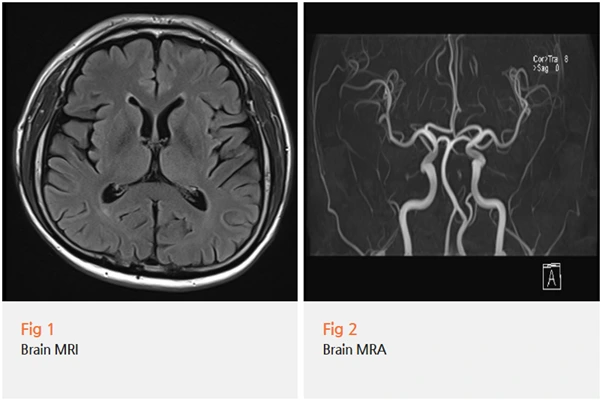

우선 중추신경계 병변을 배제하기 위해

뇌 MRI와 MRA 검사를 시행했어요.

검사 결과, 다행히 뇌에는 기질적인 문제가 없었어요.

위 환자분의 경우도 뇌 MRI로 중추신경계 문제를 배제하고,

목 MRI로 경추 문제를 확인했기 때문에

정확한 치료 방향을 잡을 수 있었던 거예요.